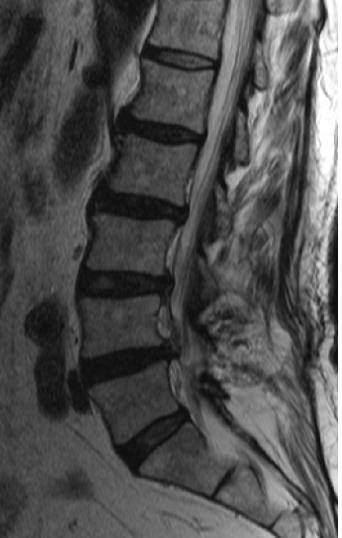

이씨에게 원리침도는 마지막 희망이나 마찬가지였다. 서울의 유명하다는 대학병원과 전문병원을 다 돌았는데 조금도 효과가 없었다. 원인을 모르겠다는 답변만 돌아왔다. 원리침도 시술 직전 밝혀진 그의 질환은 협착증 수술 후유증이었다. MRI상으로 협착증 수술 당시 뼈를 잘라낸 빈 공간에 살이 들어차 신경을 누르면서 엉겨붙어 있었다. 허리수술 주변 부위에서 탈출된 디스크도 보였다.